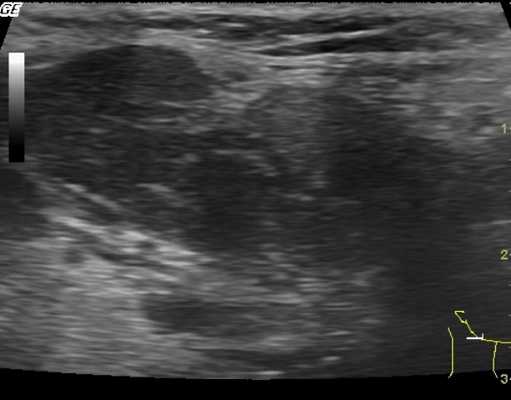

УЗИ мягких тканей бедра и голени

Ультрасонографию нижних конечностей в большинстве случаев рекомендуют пациентам с подозрением на травматические повреждения и инфекционно-воспалительные процессы. Также УЗИ применяют в комплексной диагностике злокачественных опухолей, локализующихся не только в длинных трубчатых костях обсуждаемой области, но и в прилежащих мягких тканях.

В большинстве случаев здесь выявляют саркомы - агрессивно текущие, склонные к развитию рецидивов и метастазированию новообразования. Указанные особенности делают крайне важным своевременное установление онкологического диагноза и назначение комплексного лечения.